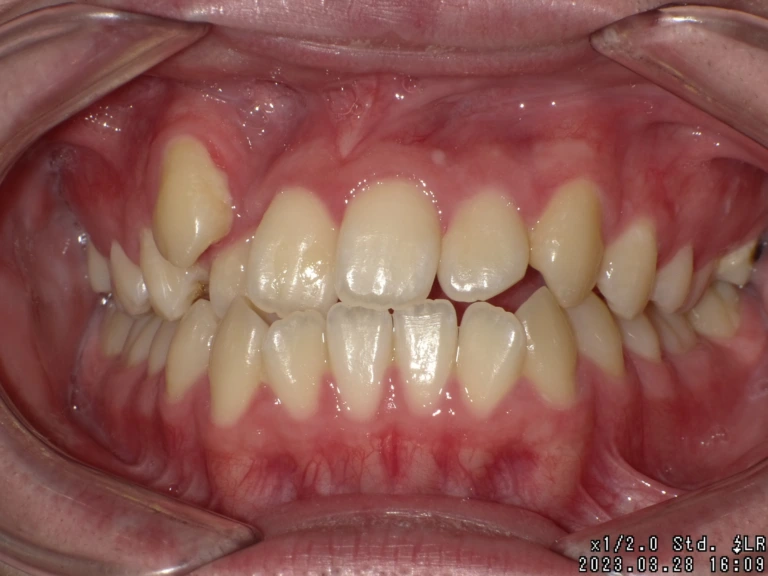

歯がガタガタ

(らんぐい歯) -

八重歯